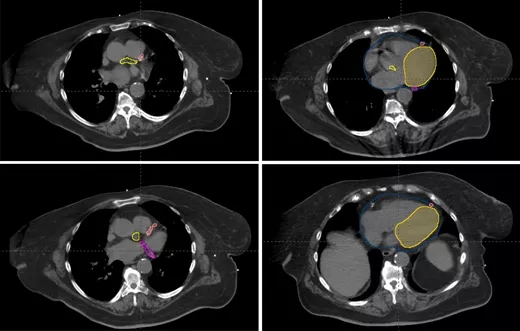

乳腺癌保乳术后放疗,左侧乳腺癌保乳术后质子治疗和传统光子放疗对比放疗在乳腺癌的治疗中起着不可或缺的作用。保乳术后,肿瘤被切除的同时尽可能多的保留了患者正常的乳腺组织。全乳照射是一个标准的后续治疗方法,某些情况下,还需要对区域淋巴结和/或肿瘤腔进行照射。随着早期乳腺癌患者存活率的提高,考虑接受此类放疗患者的潜在长期并发症变得非常重要。特别是对于左侧乳腺的放疗,